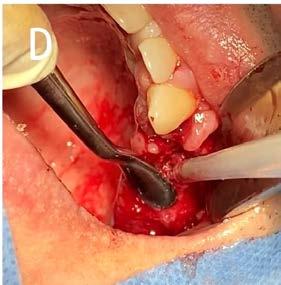

7. A) Extracción de órganos dentarios sin salvación. B) Legrado alveolar. C) Exéresis de tejido hiperplásico.

D) Sinéresis de los tejidos.

Posteriormente se abordó la fase quirúrgica: se realizaron las extracciones de los órganos dentarios sin posibilidad de mantenerse en función en boca, se efectuó el legrado alveolar para retirar tejido infectado, además de realizar la exéresis del tejido hiperplásico, y regularización ósea para posteriormente producir la sinéresis de los tejidos a través de una sutura continua simple con sutura absorbible Vicryl 3-0 (Figura 7).